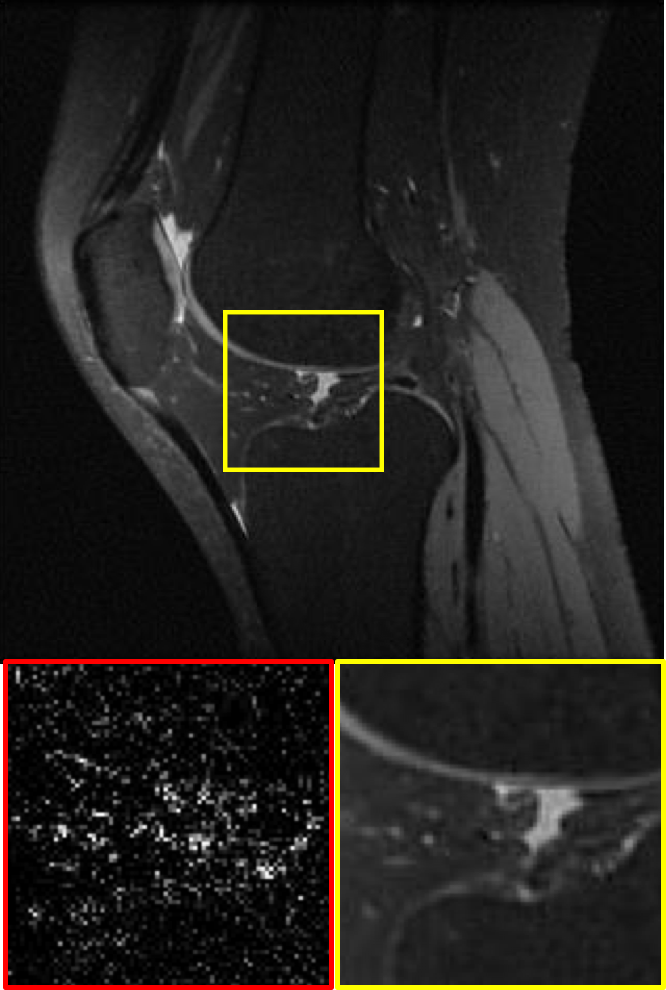

CS MR measurement matrix

LDAMP SURE was applied to CS-MRI reconstruction problem to demonstrate its generality and to show its performance on images that contain structures different from natural image dataset. We compared LDAMP SURE with state-of-the-art BM3D-AMP-MRI algorithm [16] for CS-MR image reconstruction along with TVAL3, BM3D-AMP, and dictionary learning method or DL-MRI [34]. Average image recovery PSNRs and run times are tabulated in Table 3. Figure 5 shows that our proposed method yielded state-of-the-art performance, close to the ground truth. The results reveal that proposed LDAMP SURE-T outperforms existing algorithms in all sampling ratios.

Ground truth

TVAL3

BM3D-AMP

NLR-CS

LDAMP SURE

LDAMP SURE-T

Ground truth

TVAL3

BM3D-AMP

DL-MRI

BM3D-AMP-MRI

LDAMP SURE-T